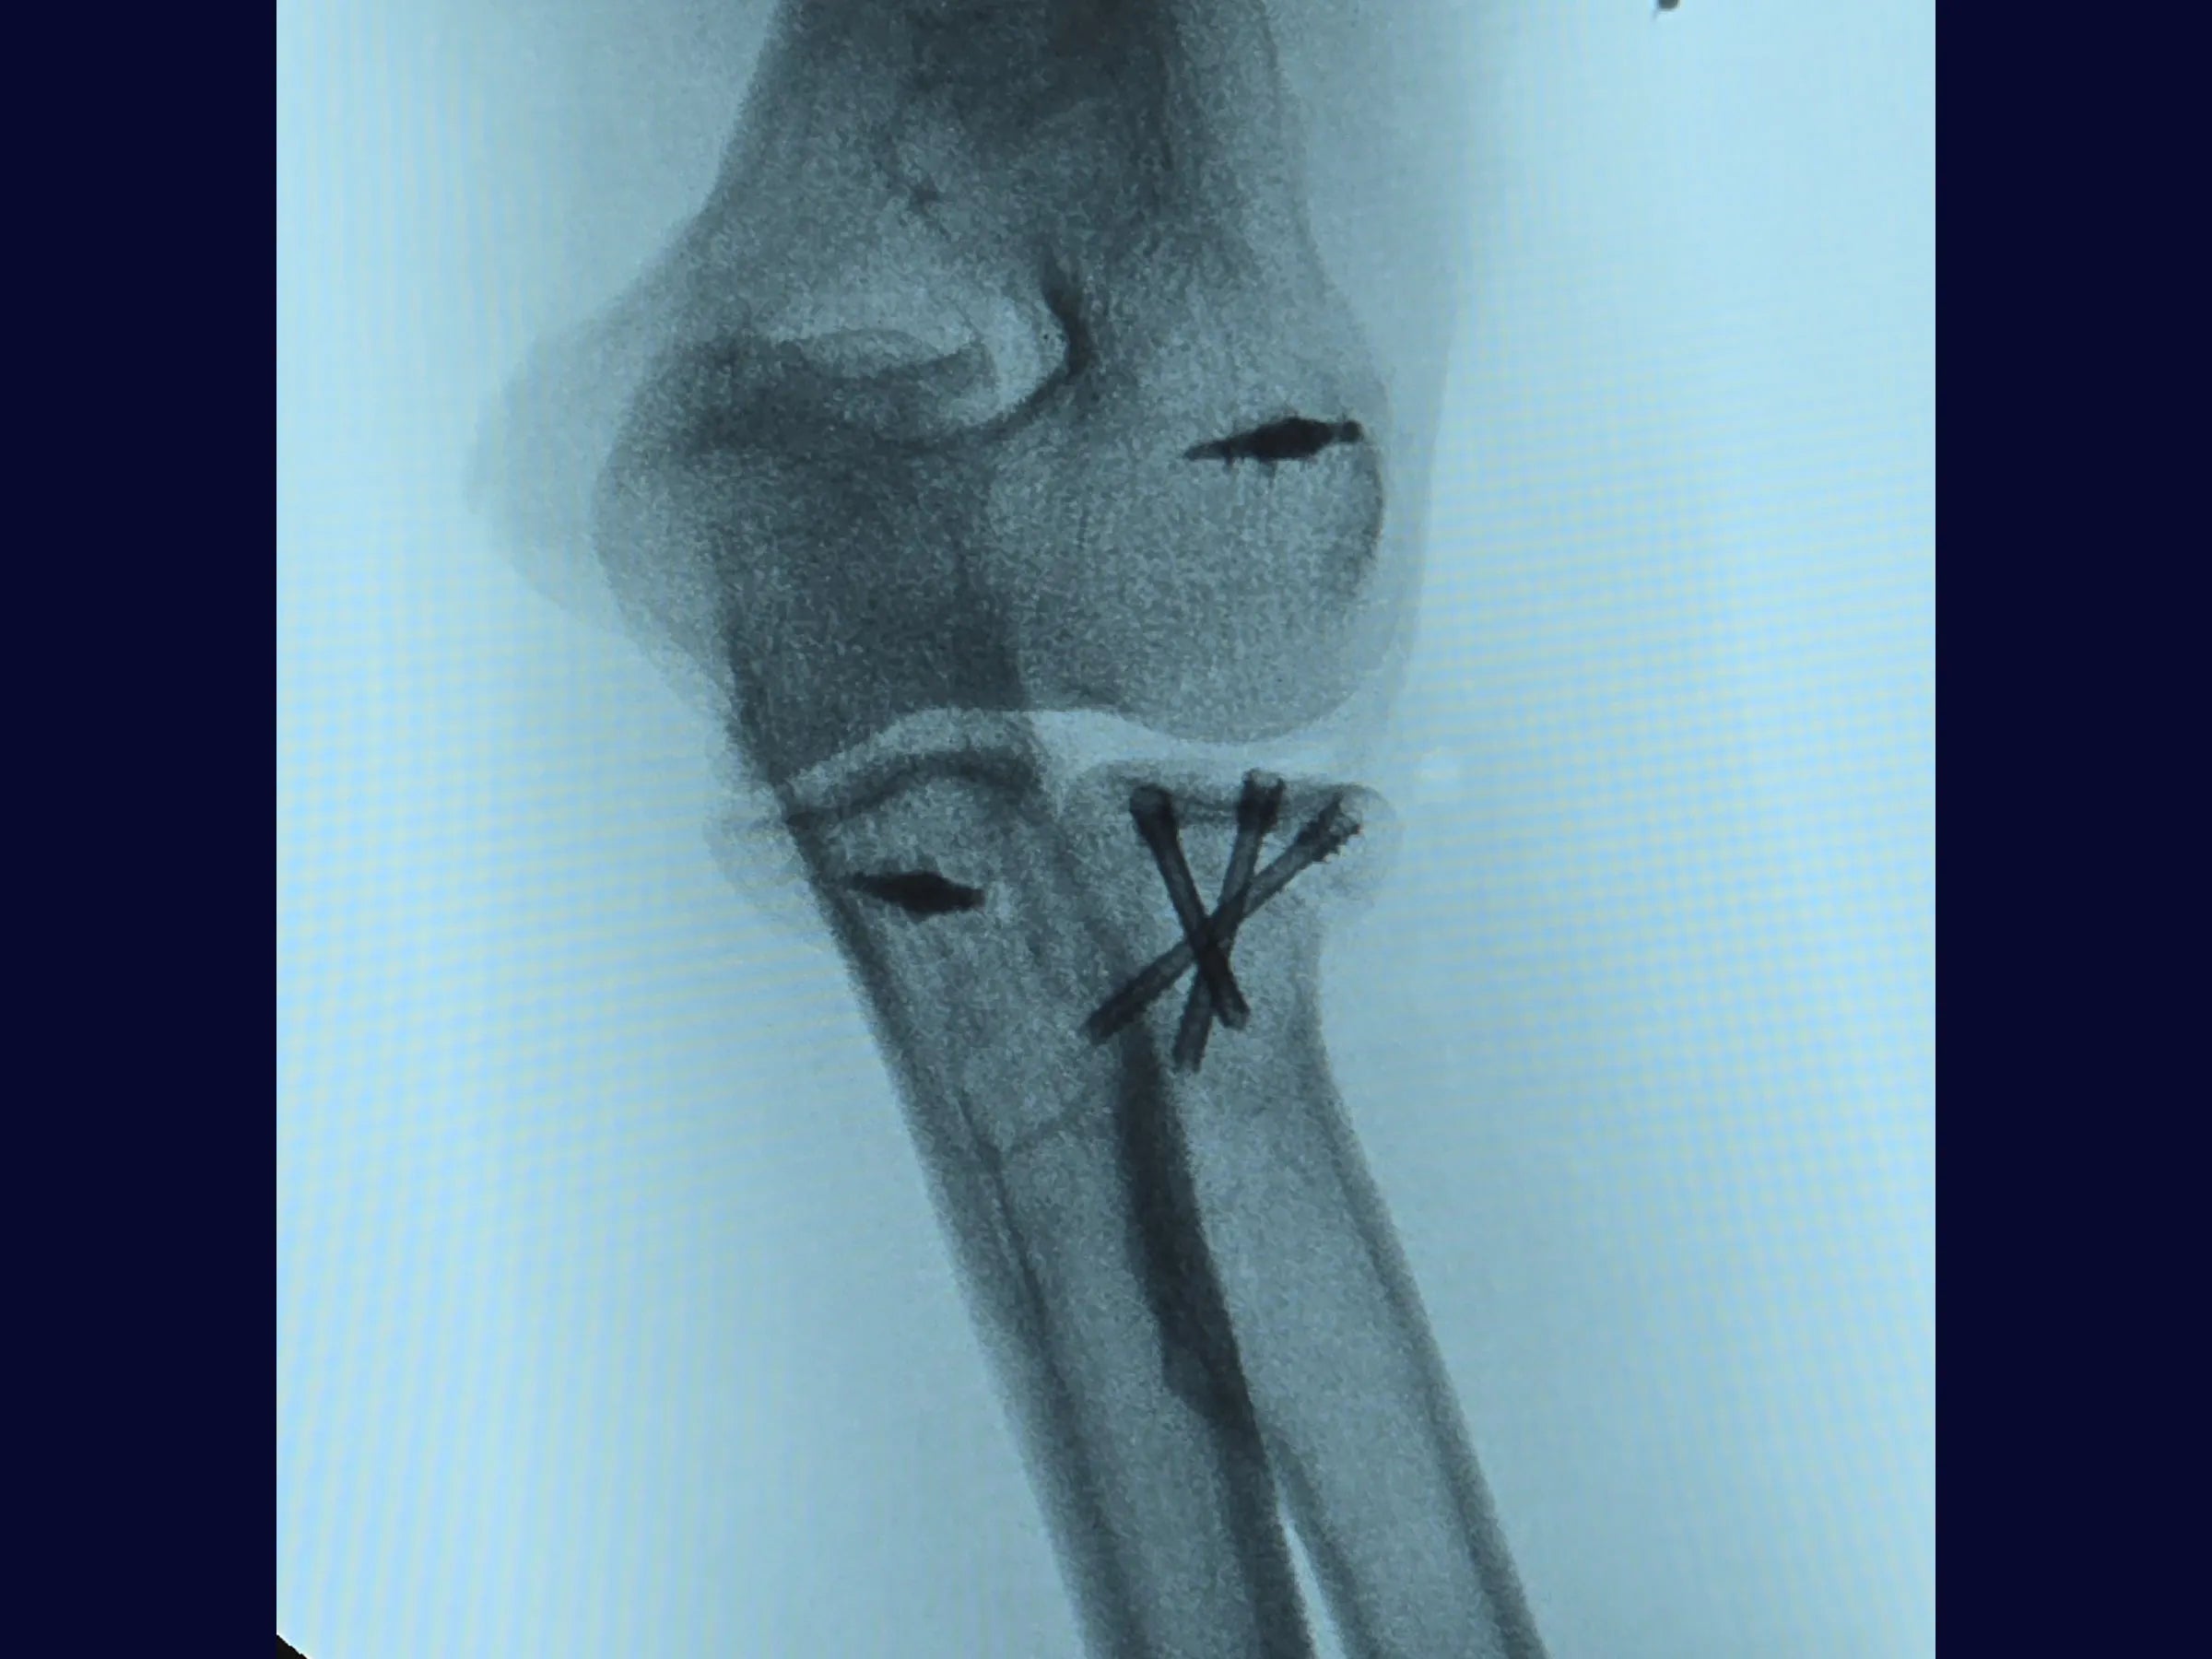

Este treinamento apresenta a técnica do tripé com parafusos de dupla compressão e reinserção capsular com âncora metálica, em vídeo 4K sob a perspectiva cirúrgica, permitindo compreender cada detalhe técnico e aplicar com segurança na prática.

- Técnica do tripé com parafusos de dupla compressão (2,4 mm).

- Fixação Segura: Parafusos sepultados em ângulo biomecânico de 45°.